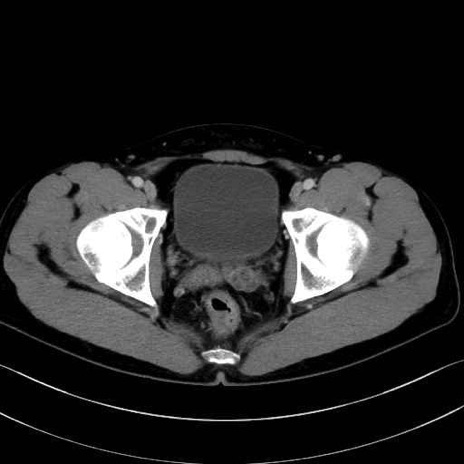

恥骨筋(pubic muscle) のCT画像の解剖

恥骨筋 (Pectineus)